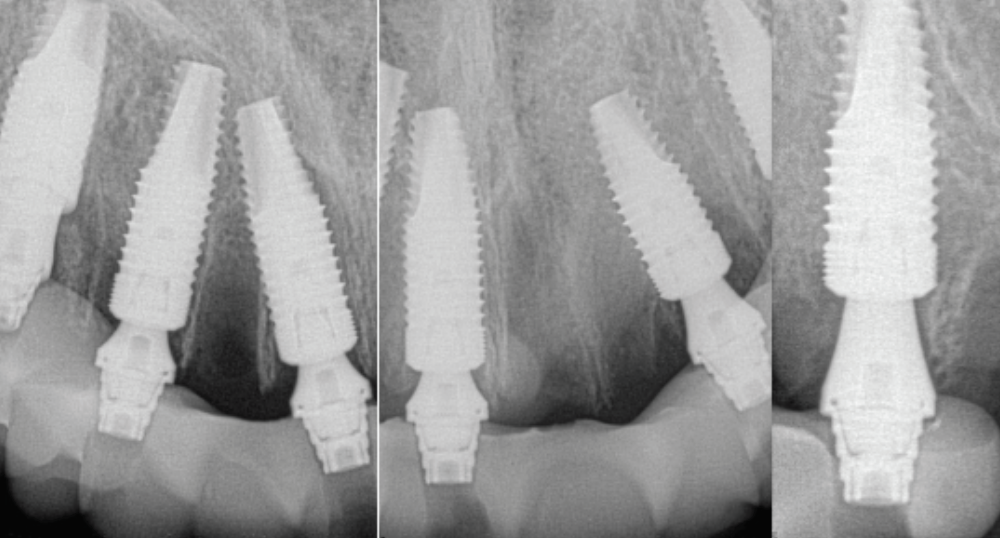

Fig 41. Postoperative periapical x-rays on the day of surgery demonstrating ideal immediate implant placement in bone.

Figure 41

Fig 42. Postoperative periapical x-rays on the day of surgery demonstrating ideal immediate implant placement in bone.

Figure 42

At the completion of surgery for the mandibular arch, teeth Nos. 17, 21 through 24, and 27 through 30 had been carefully extracted. Immediate implants with multi-unit abutments were placed in sites Nos. 21, 24, 28, and 30, and an additional implant with a multi-unit abutment was placed in site No. 18. All multi-unit abutments were torqued to 30 Ncm. In the maxillary arch, at the completion of surgery, teeth Nos. 2 through 15 had been carefully extracted. Immediate implants with multi-unit abutments were placed in sites Nos. 4, 6, 8, 11, and 13, and all multi-unit abutments were torqued to 30 Ncm.

The completed prosthesis was then screwed directly onto the multi-unit abutments with Rosen screws with no ti-bases and torqued to 20 Ncm. Screw-access holes were filled, and no occlusal adjustment was necessary. The fit of the prosthesis was precise and stable and the phonetics of the patient was ideal. The patient was overwhelmed by the significant esthetic improvement with this set of teeth in place.